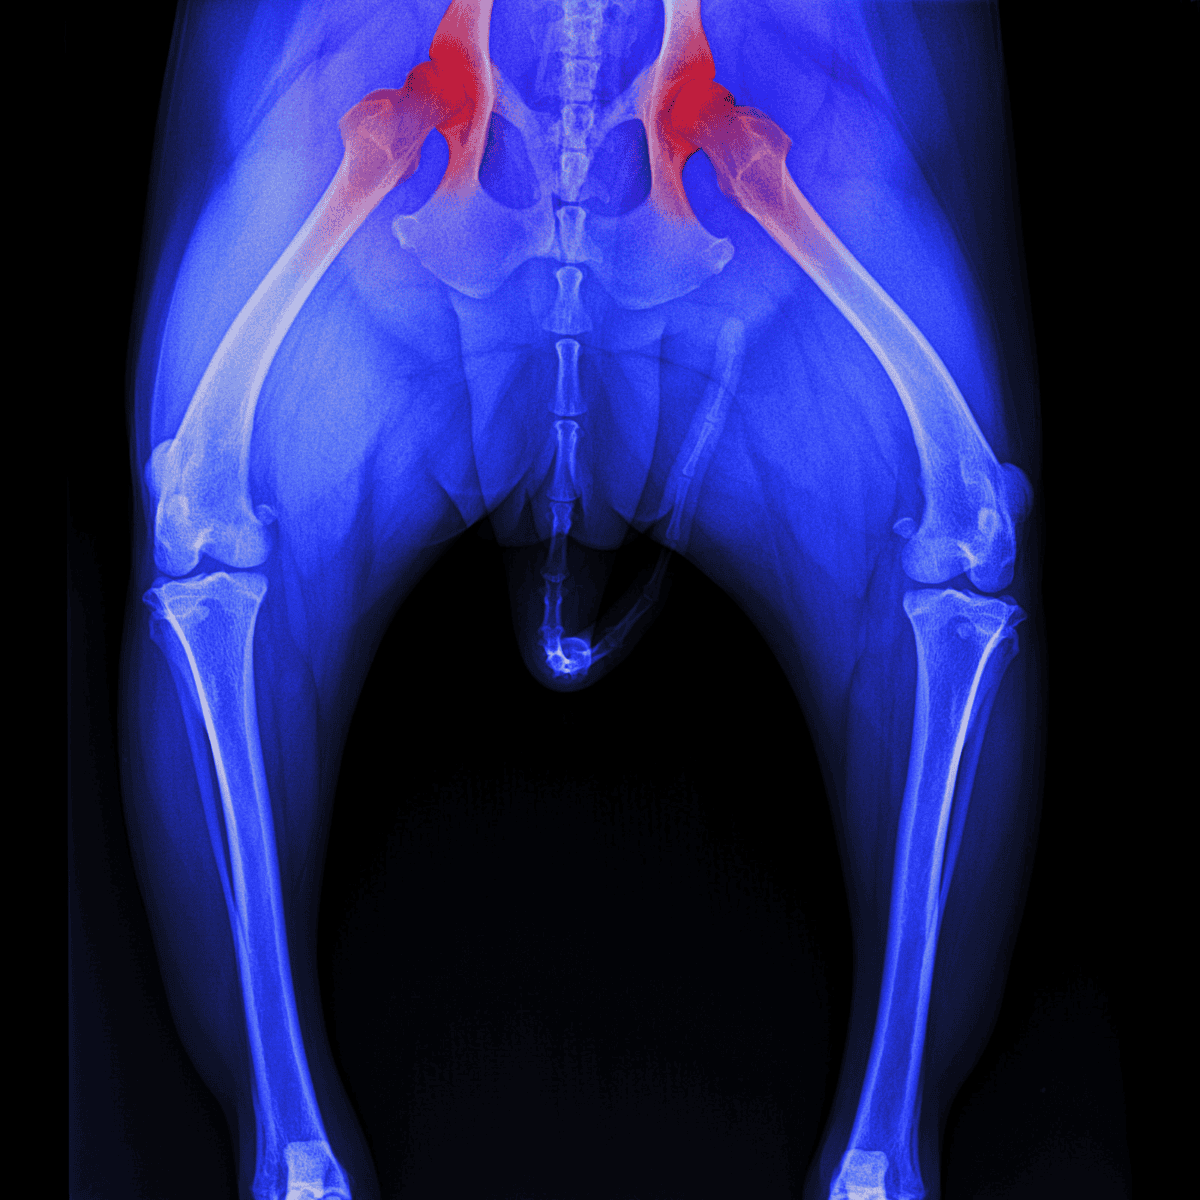

Chronic pain results from long-term conditions such as arthritis, cancer, or hip dysplasia. It is persistent and may worsen over time, causing significant stress to your dog and negatively impacting their quality of life.

Anti-inflammatory drugs can be prescribed for surgeries and long-term conditions like hip dysplasia, and osteoarthritis. These can also be used safely with medications like tramadol, gabapentin, or joint supplements.